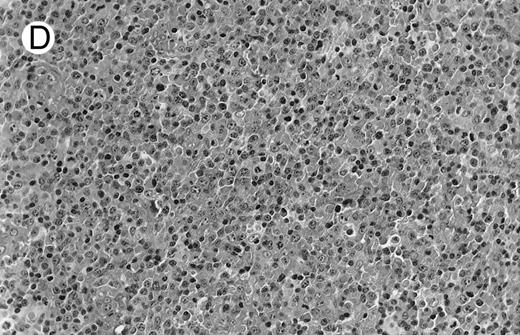

Low-grade marginal zone B-cell lymphoma (MZL; REAL classification)9 comprised the largest number of cases (n = 12). Nine of them were low-grade MALT type lymphomas involving parotid, stomach, bronchus, buccal mucosa, and skin. The histological pattern was relatively homogeneous, showing diffuse lymphoid infiltrates that included small lymphocytes with round nuclei or with plasma-cell differentiation and/or centrocyte-like cells with indented nuclei (Fig 1A). Lymphoepithelial lesions were observed in each case, regardless of the tissue involved (Fig 1B). Monocytoid cells characterized by a larger cytoplasm and a slightly irregular nucleus were mixed with centrocyte-like cells in 2 cases of MALT lymphoma arising in the parotid (cases no. 3 and 15). There were also scattered occasional large cells (centroblast or immunoblast). In cases no. 3, 6, and 15, remnants of germinal centers with partial follicular colonization were observed (Fig 1C). Beside these 9 low-grade-type mucosal lymphomas, 3 nodal lymphomas (cases no. 8, 10, and 14) had histological features similar to that of low-grade MALT type lymphoma because they showed a typical lymphoplasmacytoid infiltration with a variable proportion of blasts. In 2 cases, the presence of numerous immunoblasts or centroblasts, mixed with small lymphoplasmacytoid cells or plasma cells, indicated an evolution to a more aggressive lymphoma (Fig 1D). The third nodal lymphoma showed a small lymphocytic or lymphoplasmacytoid diffuse infiltrate associated with intrasinusal large nests of monocytoid cells. This histological picture is characteristic of monocytoid B-cell lymphoma (MBLC; Fig 1E).

(D) Case no. 10. Immunocytoma in lymph node. The infiltrate is composed of small lymphocytes, plasma cells and blasts. (E) Case no. 14. Monocytoid B-cell lymphoma in a cervical lymph node with a monocytoid component located in dilated sinuses.